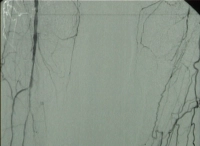

DAOP perna direita grau IV de Fontaine, perna esquerda grau III com:

- Arteriosclerose de alto grau da aorta terminal e de ambas as artérias ilíacas

- Oclusão estendida de ambas as artérias femorais superficiais

- Oclusão parcial das artérias infrapoplíteas em ambas as pernas

DSA pré-operatória: